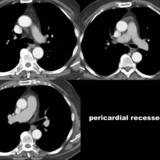

recesses

Date: 07/24/2006

Views: 3049